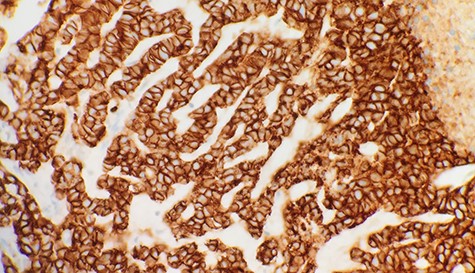

A 67-year-old female presented in early 2018 with right breast ACC previously diagnosed via diagnostic core biopsy showing invasive ACC with basaloid features in late 2017. She underwent a right modified radical mastectomy with level I lymph node dissection at this time. The pathology report demonstrated a mass measuring 3.5 × 3.5 × 2.5 with a nuclear grade of II/III. The tumor margins were negative for malignancy, and zero of nine lymph nodes showed involvement. Immunohistochemistry for the breast tumor was positive for CK5/6, p63 and MYB, and negative for ER, PR and CD11. She refused adjuvant radiation and chemotherapy at that time and was discharged. In 2019, the patient presented to the emergency department complaining of right upper quadrant abdominal pain, pruritus and darkening of the skin, urine and sclera. A computed tomography scan of the chest, abdomen and pelvis showed extensive hepatic and splenic lesions, and a bone scan showed multiple focal bony lesions suggestive of metastasis. The biopsy of the liver mass was consistent with invasive ACC (Fig. 1), and immunohistochemical stains of the liver mass showed positive mammaglobin, CDX2, CK7 and p63. MYB, CD117, CD56, PAX8, TTF1, Napsin A and CK20 stains were negative. Cells were positive for E-cadherin (Fig. 2), supporting the breast primary. The patient was diagnosed with metastatic breast adenoid carcinoma in the liver and spleen and was referred to palliative care for end of life care.

Immunohistochemical stain reveals that tumor cells are positive for E-Cadherin (IHC x40).